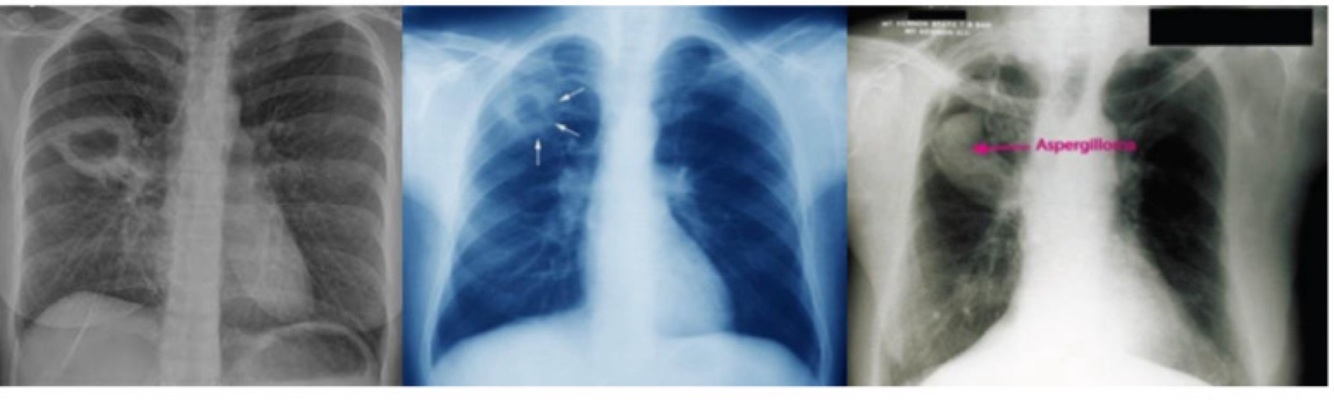

Adultos e adolescentes.

TB PÓS-PRIMÁRIA – bacilífera :

•Adolescente/adulto – reativação ou reinfecção

•Tosse prolongada, febre vespertina, sudorese noturna, perda de peso

•RX: infiltrado + cavitação

•Complicação: Aspergiloma (bola fúngica)